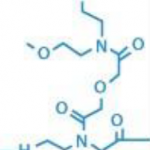

- PNAsTM miRNA 抑制剂和阴性对照PANAGENE公司用PNA开发了比目前其他抑制剂特异性和稳定性更好的抑制剂-PNAs™ miRNA 抑制剂。PNAs™ miRNA 抑制剂是单链的PNA,特异性的与内源性miRNA结……阅读更多:PNAsTM miRNA 抑制剂和阴性对照

- PNA端粒 FISH探针肽核酸 (PNA, peptide nucleic acid)是一种全新的DNA类似物,可以识别并结合 DNA或 RNA序列,形成稳定的双螺旋结构。由于PNA不带负电荷,……阅读更多:PNA端粒 FISH探针